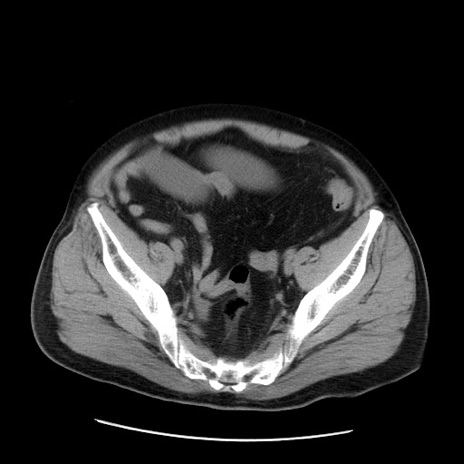

症例20(横断像)

【症例】 60歳代男性

【主訴】 腹部膨満、嘔吐

【現病歴】5日前頃より倦怠感を認め食事量減少し4日前の朝嘔吐、食事摂取困難となった。 3日前近医受診し点滴施行され整腸剤などを処方された。 当日他院を受診し、腹部膨満著明、炎症反応の上昇(CRP10.8、WBC11200)あり、紹介受診となる。

【既往歴】 躁うつ病(抗精神病薬多数内服あり)

【身体所見】 意識JCS1 受け答えがはっきりしないBP 111/57mHg、 P 67bpm、、BT35.2°C、SpO2 97%(RA)、 腹部:膨隆、打診で鼓音あり、全体的に圧痛有り、腸蠕動音(-)、反跳痛ははっきりせず。

【データ】WBC 11400、CRP 14.20